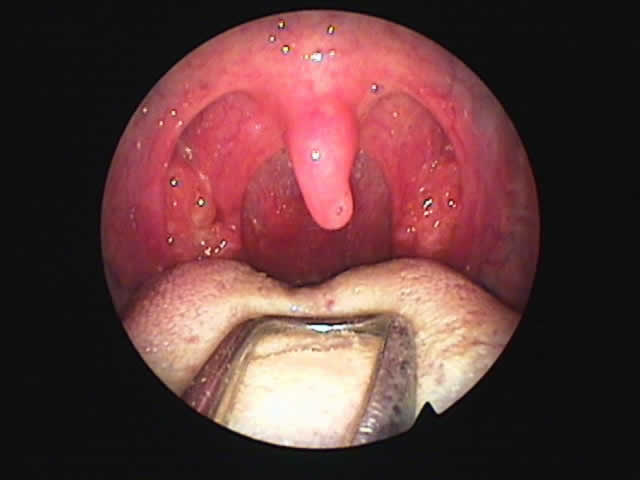

| 7月16日 かなり縮小 | 両手術直後(縮小不十分なため追加焼灼、8月9日) | 9月8日 著明に縮小しいびき消失しているとのことです |